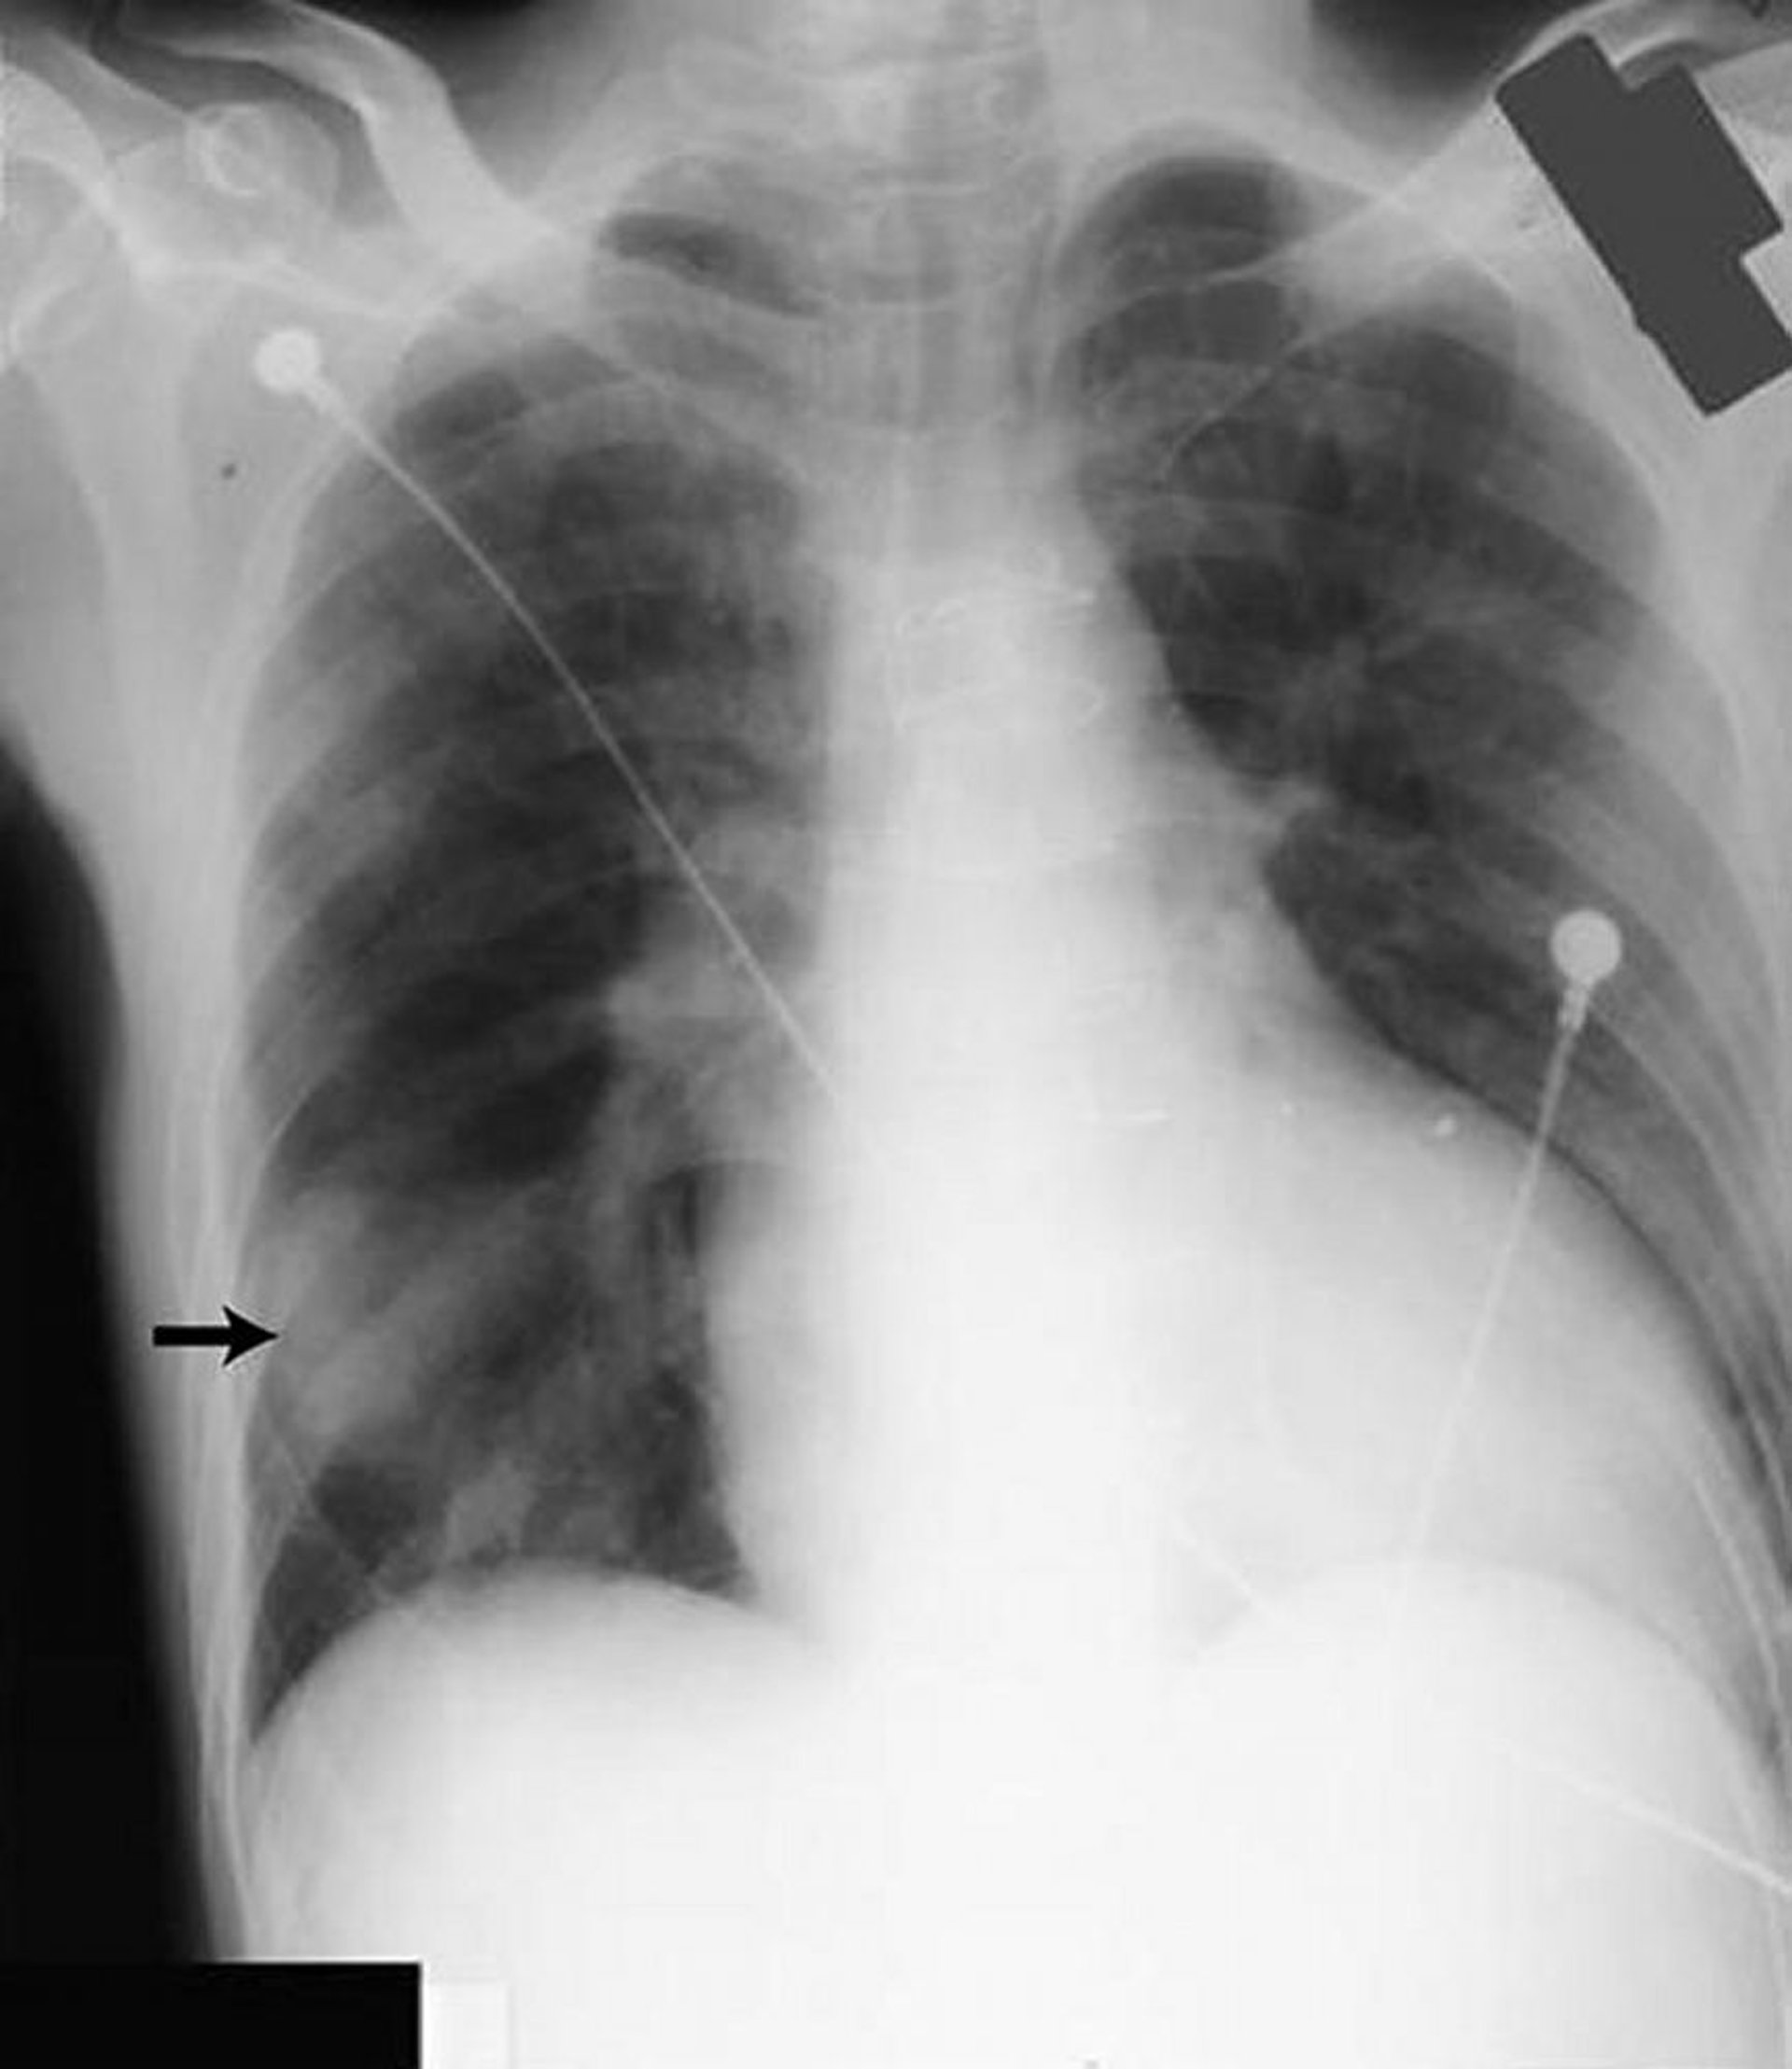

Opacity in the right lower lung field (arrow) resembles a solid mass but was caused by fluid in the major fissure in a patient with heart failure.

By permission of the publisher. From Huggins J, Sahn S. In Bone's Atlas of Pulmonary and Critical Care Medicine. Edited by J Crapo. Philadelphia, Current Medicine, 2005.